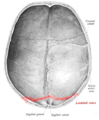

Lambdoid suture

![]() Lambdoid suture (shown in red line) | |

The lambdoid suture (or lambdoidal suture) is a dense, fibrous connective tissue joint on the posterior aspect of the skull that connects the parietal bones with the occipital bone. It is continuous with the occipitomastoid suture.

Its name comes from its lambda-like shape.

The lambdoidal suture articulates with the occipital bone and parietal bones.